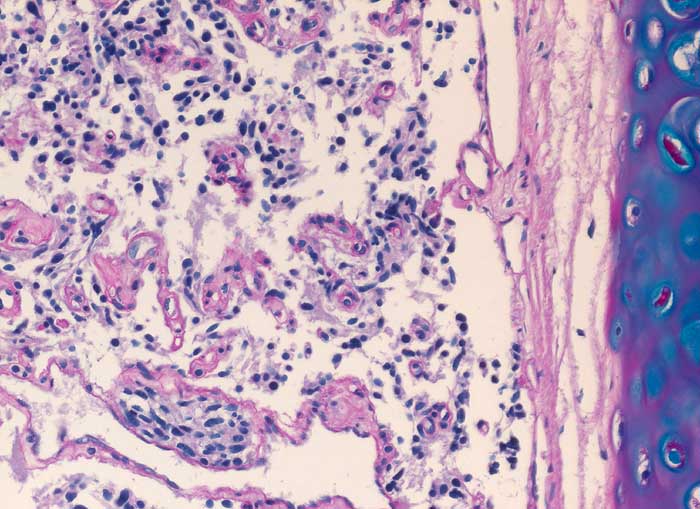

PathoPic ID 6337 - Karzinoid

Karzinoid

benigner Tumor

Lunge

Lunge, Mediastinum mit Thymus

Spindelzellige Tumorzellnester bilden kleine von schmalen Bindegewebssepten mit Kapillaren umgebene Zellnester. Der Tumor infiltriert die Submukosa.

Da es sich nur um eine sehr kleine Biopsie handelt, kann ein atypisches Karzinoid (Nekrosen, Mitosen) nicht ausgeschlossen werden.

Histologie

200